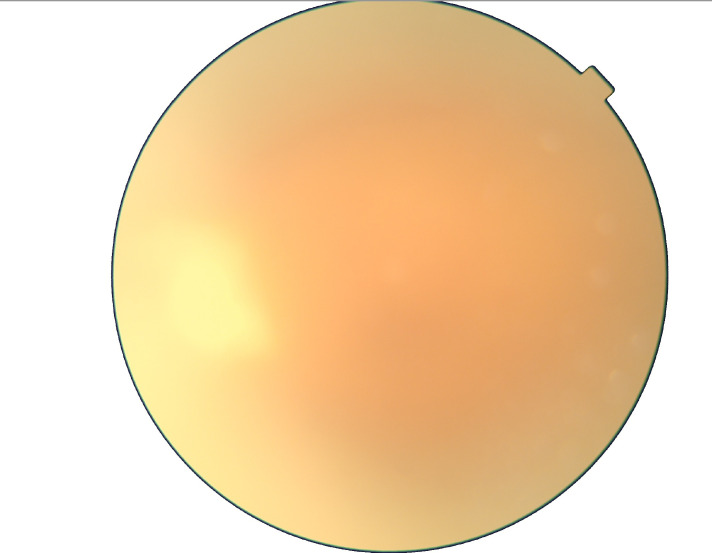

Systemic fluconazole was used with consent from a nephrologist. Intravitreal voriconazole was used in the dose of 0.1 mg/0.1 mL Use of intravitreal voriconazole was reported earlier with favourable results in Cryptococcus sp. We decided to combined use of intravitreal voriconazole and systemic fluconazole. The intravitreal injections of voriconazole were repeated every 3 days and the patient was continued on oral fluconazole 200 mg two times per day and reviewed at weekly interval patient received four doses of intravitreal voriconazole. At the last follow-up of 2 months, VA in the left eye improved to 6/24 and there was complete resolution of disc granuloma and vitritis (figure 8). Left eye fundus showed diffuse epiretinal membrane, diffuse cystoid macular oedema confirmed by optical coherence tomography of the left eye (figure 9).

Figure 8.

At the last follow-up fundus photograph shows few dot hemorages and complete resolution of disc granuloma with epiretinal membrane at the macula.